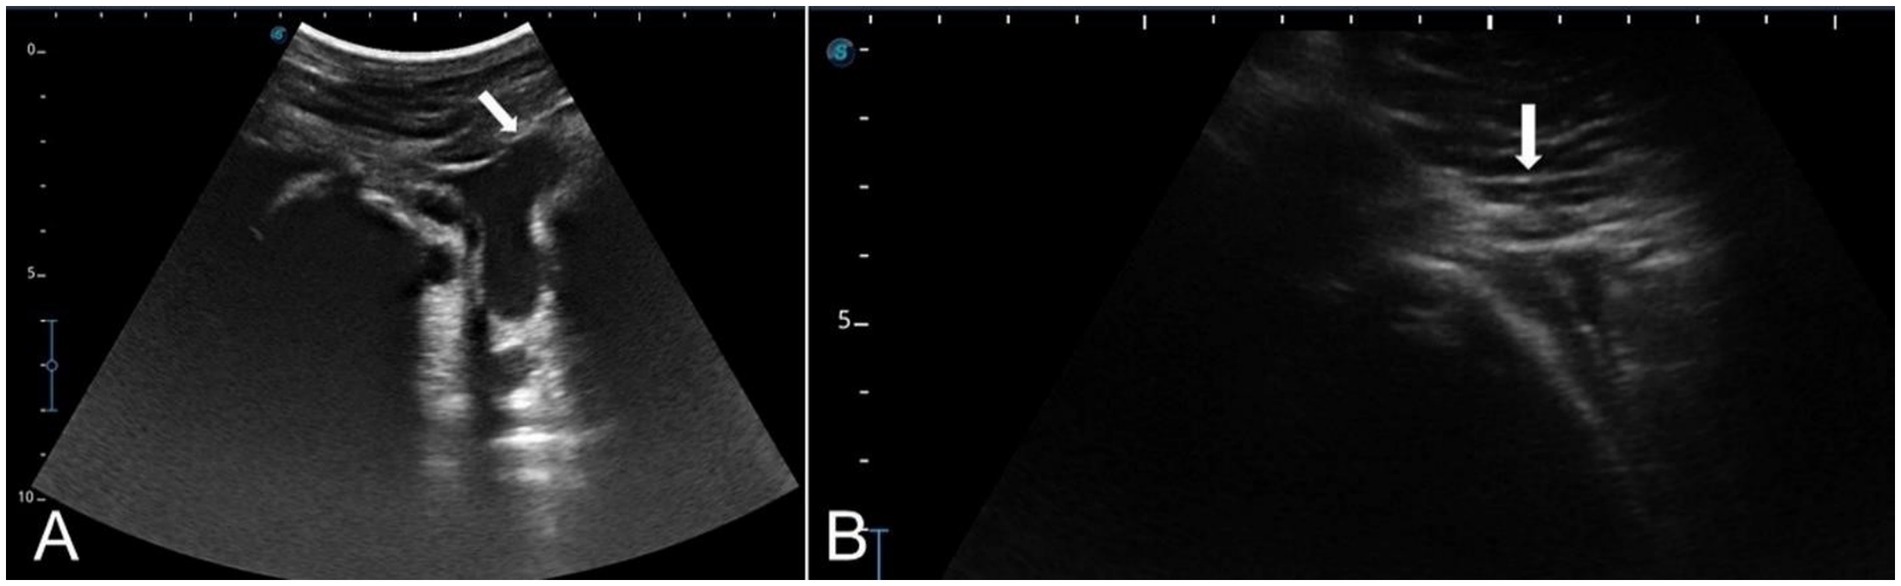

Each nerve of the dromedary camel’s ear could be precisely discriminated using anatomical and ultrasonographic-guided techniques. The anatomical landmarks determining the point of needle insertion for the internal and great auricular nerves were successfully identified and confirmed by ultrasonography (Figures 9A,B). Based on the anatomical and ultrasonographic landmarks, the site of injection for the internal and great auricular nerves was approached at the lateral side of the base of the auricular cartilage and the base of the pinna on its caudal side, respectively.

Ultrasound images labeled A and B show anatomical structures with distinct white arrows pointing to specific areas. Image A displays a cross-sectional view highlighting a central structure, while image B shows a different angle with details indicated by the arrow. Both images feature scale markings on the sides.

Figure 9. Linear ultrasound images showing the auricular nerve at the distal third of a live camel’s ear. (A) Great auricular nerve. (B) Internal auricular nerve.